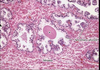

1

Q

A

ovary